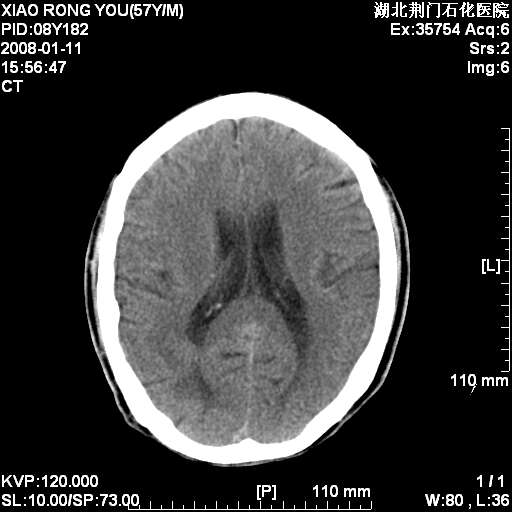

1月后复查

多发,考虑转移

多发转移!

考虑为:多发转移瘤可能性大。

病变范围在一个多月时间增大,且密度不均周围有税种,并且多发!考虑转移瘤!